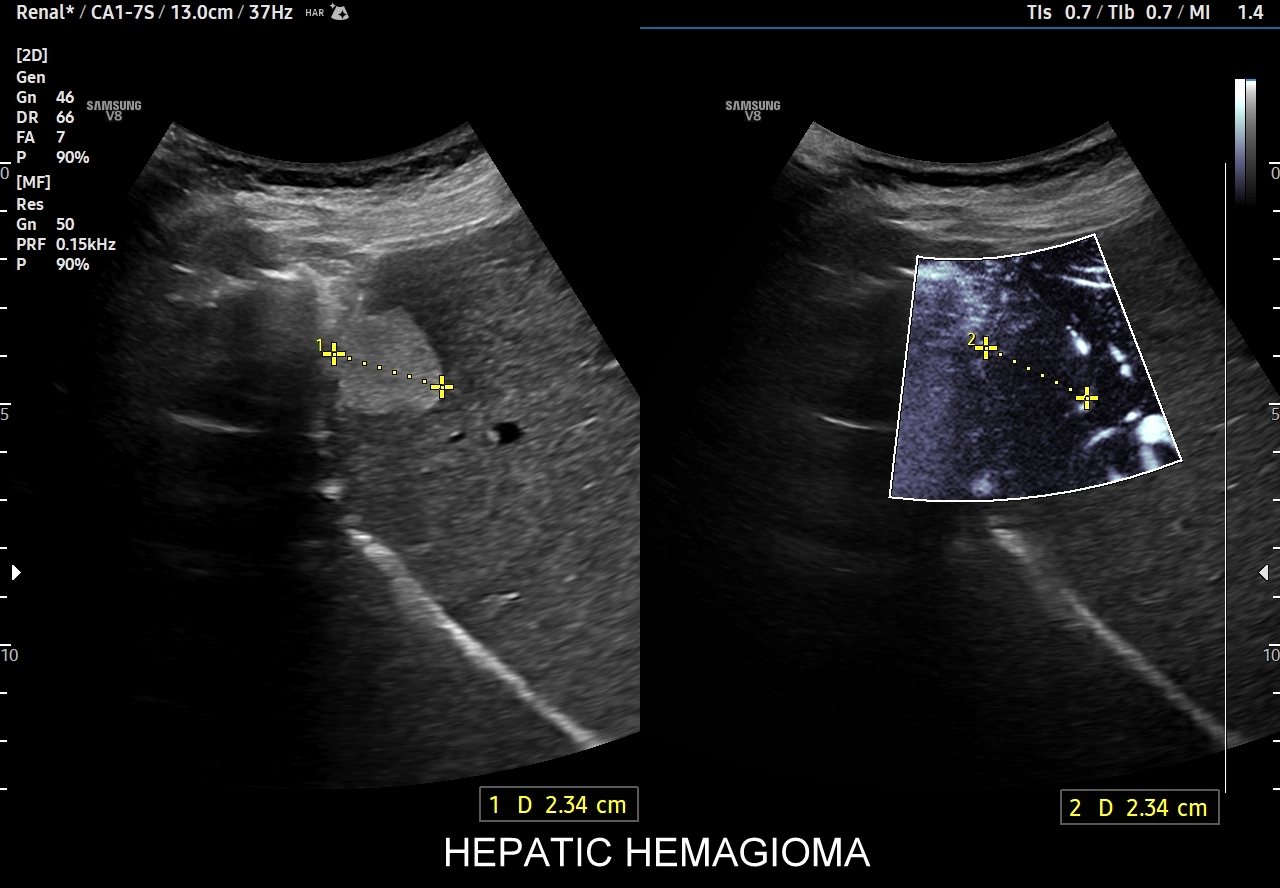

W badaniu USG w prezentacji B w niestłuszczonej wątrobie typowy naczyniak włośniczkowy lokalizuje się w pobliżu gałęzi żyły wątrobowej, a prezentuje się jako ostrookonturowana, hyperechogenna, jednorodna, krągła lub owalna zmiana ogniskowa. Ze względu na niską prędkość przepływu krwi i wynikające z tego ograniczenie detekcji w trybie color-Doppler w naczyniaku nie rejestruje się sygnału. Z kolei w trybie mikrounaczynienia (MVI / MVF) w zależności od czułości aparatury w naczyniaku można zaobserwować delikatny sygnał w postaci „poprószonego śniegu”.

W przypadku zarejestrowania w obrębie hyperechogennej zmiany ogniskowej wątroby w trybie kolorowego Dopplera lub Dopplera mocy (ang. power Doppler) drobnego naczynia lub naczyń, w szczególności krętych i o nieregularnym przebiegu, należy brać pod uwagę prawdopodobieństwo obecności złośliwej zmiany metastatycznej lub innego rodzaju zmiany ogniskowej.

Naczyniaki duże, tj. powyżej 2-3 cm, mogą mieć strukturę niejednorodną echogenicznie, w tym obszary hypoechogenne. Spotyka się także naczyniaki o charakterystyce normo- lub hypechogenicznej, w szczególności w wątrobie stłuszczonej. Z powyższych względów należy mieć na uwadze i zapamiętać, że badanie USG w podstawowym trybie B nie jest wystarczające do postawienia rozpoznania naczyniaka wątroby. W ramach obrazowej diagnostyki różnicowej najbardziej pomocnym jest badanie USG z kontrastem (CEUS), w którym to naczyniak wątroby posiada charakterystyczny wzorzec wypełnienia.